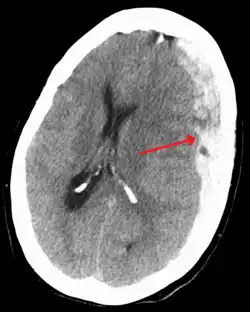

Ematoma subdurale fronto-parietale sinistro, indicato con la freccia, associato a uno spostamento a destra del tessuto cerebrale e ad una emorragia biventricolare a livello dei corpi dei ventricoli laterali (iperdensità intraventricolare)

Le cause non traumatiche dell'ematoma sono spesso conseguenza di alterazioni della coagulazione del sangue (ictus, ischemia cerebrale, aneurisma, emorragia, coagulo, trombo), presenza di tumore cerebrale o conseguenze di operazioni di neurochirurgia. Formato da sangue venoso, se va a comprimere le strutture del sistema ventricolare può bloccare il deflusso del liquor dando origine all'idrocefalo ostruttivo. La diagnosi può essere accertata tramite una semplice TC cranica senza mezzo di contrasto che evidenzierà, nel caso di un ematoma subdurale acuto un’area iperdensa (cioè più chiara rispetto al tessuto cerebrale circostante) a forma di falce, adiacente alla teca cranica.

Nel caso in cui l’ematoma subdurale sia cronico si evidenzierà un’area ipodensa (cioè più scura rispetto al tessuto cerebrale circostante).